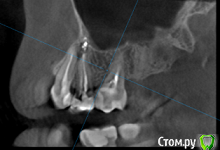

St. Опубликовано 26 августа, 2016 Поделиться Опубликовано 26 августа, 2016 Все три пролечены не очень хорошо, в идеале перелечить и сделать на них коронки. Но на сладкое ни один из них не может реагировать. Возможно реагирует 7 или 3, у которых оголена часть корней за счет вашего парадонтита. 1 Ссылка на комментарий

Гарриевич Опубликовано 27 августа, 2016 Поделиться Опубликовано 27 августа, 2016 возможно пропущенный канал, а возможно Вам "кажется" и реагируют все таки живые зубы. В любом случае данный снимок показывает не очень качественное лечение, но это только снимок 1 Ссылка на комментарий

татьяна tat Опубликовано 27 августа, 2016 Автор Поделиться Опубликовано 27 августа, 2016 возможно пропущенный канал, а возможно Вам "кажется" и реагируют все таки живые зубы. В любом случае данный снимок показывает не очень качественное лечение, но это только снимок Ссылка на комментарий

Beznika Опубликовано 8 сентября, 2016 Поделиться Опубликовано 8 сентября, 2016 на 5 ке материал вывели за апекс. резекцию возможно придётся делать верхушки корня... + карман у вас есть за 6кой. а так всё равно перелечивать надо... масса пористая в каналах и не гомогенная. (не однородная) Ссылка на комментарий